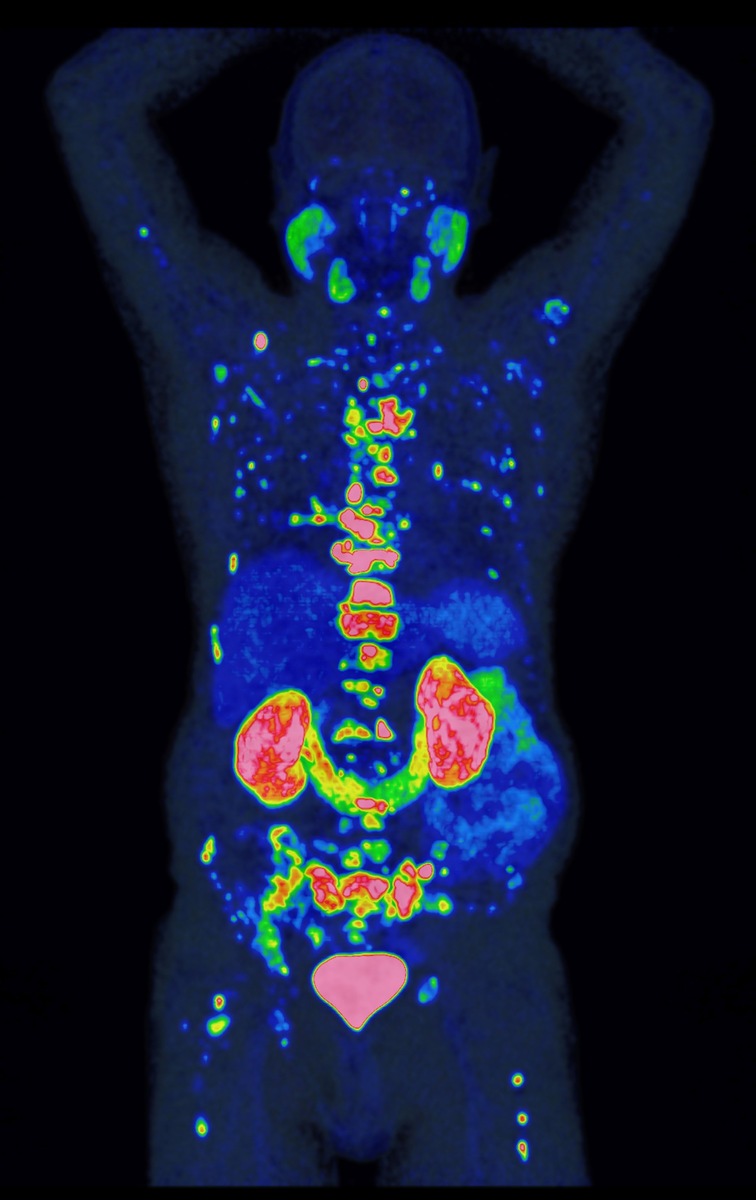

Das PROMISE-Team nutzte für die Risikobewertung die PSMA-PET**, ein hochmodernes Bildgebungsverfahren, mit dem sich Prostatakrebszellen besonders präzise und ihr Ausbreitungsstadium im Körper sichtbar machen lassen. Da die Methode empfindlicher ist als ältere Verfahren, mussten ihre Befunde zunächst in neue Behandlungsempfehlungen übersetzt werden – ein Prozess, den PROMISE maßgeblich geprägt hat. In einer der größten Studien weltweit wertete das Team Bilddaten von über 15.000 Patienten aus. Gemeinsam mit international führenden Forschungseinrichtungen entwickelte es daraus das PROMISE-Schema – eine Methode, mit der sich individuelle Risikoprofile auf Basis der PSMA-PET deutlich präziser bestimmen lassen. Darauf aufbauend entstanden Nomogramme, also Vorhersagemodelle für das individuelle Risiko, die für Ärzt:innen und Patient:innen verständlich aufbereitet und zur gemeinsamen Therapieentscheidung nutzbar sind.